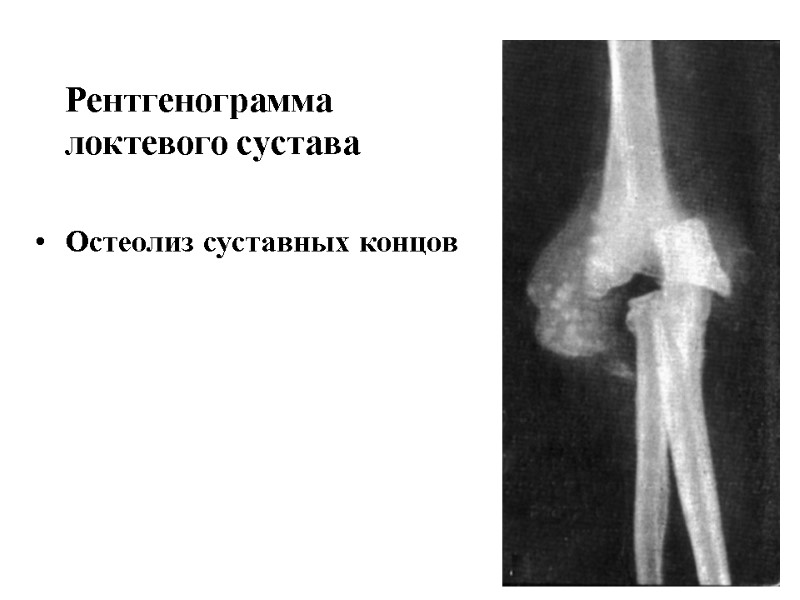

Рентгенограмма локтевого сустава Остеолиз суставных концов